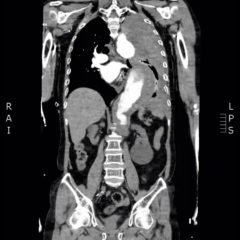

The patient hadperioral cyanosis, blue coloration around her mouth, but the rest of the skin on her face appeared normal. She also had acrocyanosis to bilateral hands that can be seen in the image. The patient has a tan complexion up to the level of her wrists, but the palms of her hands are pale and cyanotic.